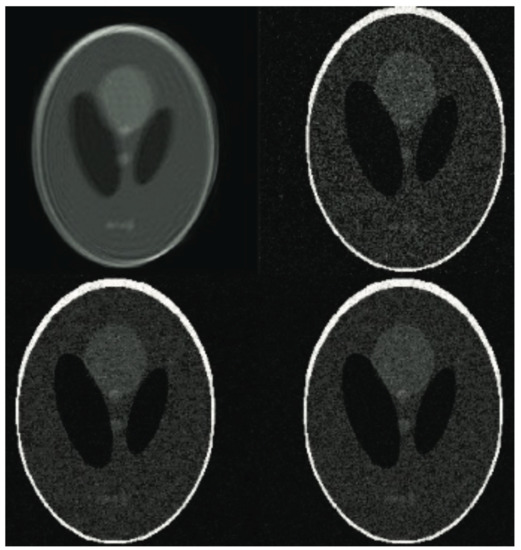

Figure 5. The phantom images based on experiment results. See from the upper row: the unprocessed image corrupted by simulated shift and the reconstructed images with various sampling rates (varying from 25% to 40% and 60% of samples of the ground truth).

In order to measure the performance of the proposed algorithm, both laboratory phantom studies and an in-vivo assessment were performed. The purpose of the experiment was to compare the effectiveness of various ways of obtaining a compressively-sensed input. In a study of the effects of various compressed-sensing ratio on test performance, the test performance of the proposed Super-Resolution Image Reconstruction method was tested. Moreover, several MRI k-space sampling patterns have been compared. Figure 5, Figure 6, Figure 7, Figure 8, Figure 9, Figure 10, Figure 11, Figure 12, Figure 13, Figure 14, Figure 15, Figure 16, Figure 17, Figure 18, Figure 19, Figure 20, Figure 21 and Figure 22 show the achieved results. It must be emphasised that combining Compressed Sensing with Hermitian symmetry property, as well as Partial Fourier allows the shortening of k-space filling when compared to the different k-space sampling schemes, see Figure 1.